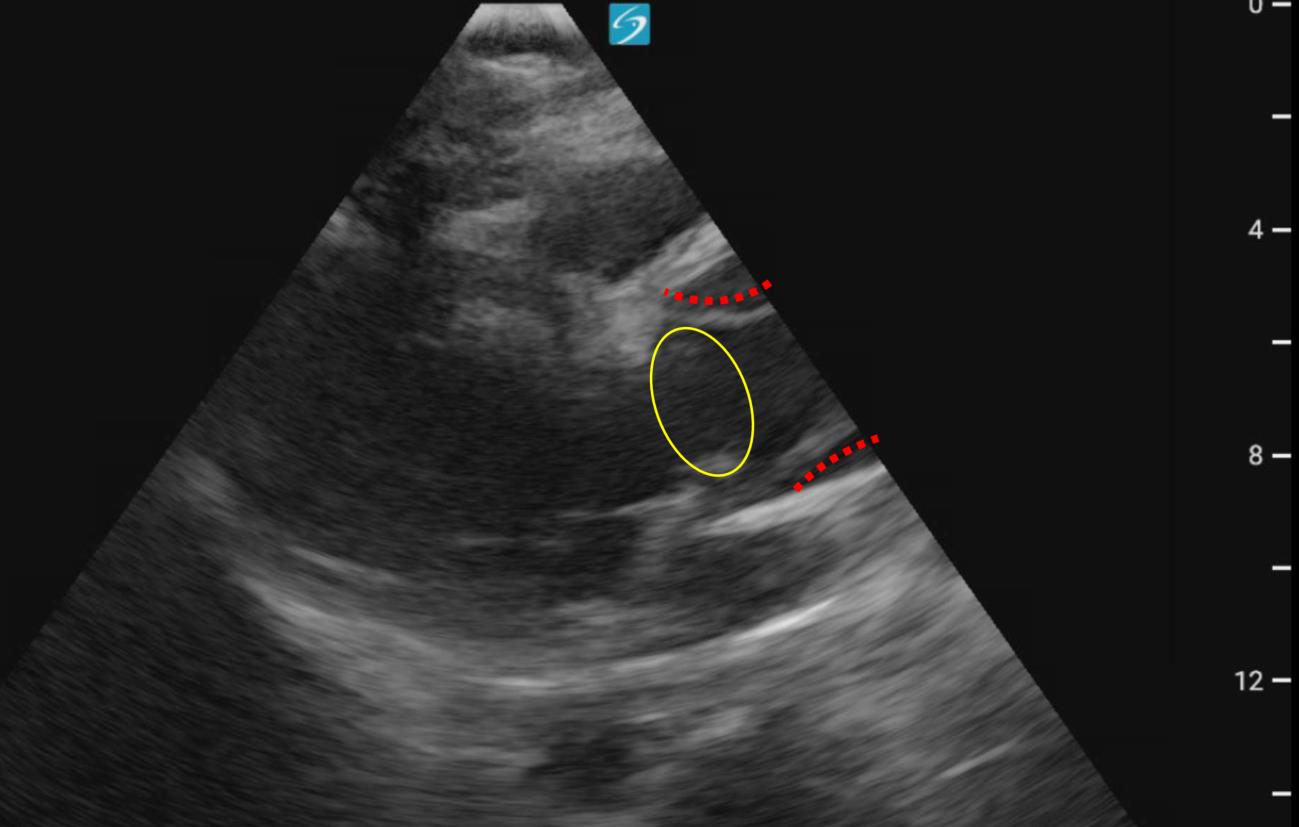

GORE_Figure2